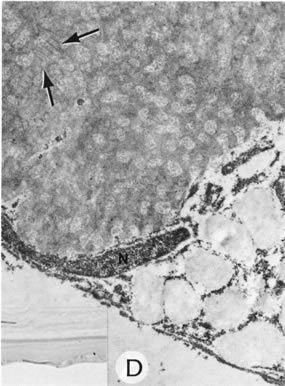

Syphilis is a venereal disease caused by the spirochete Treponema pallidum, which primarily affects the central nervous and cardiovascular systems. During the past decade, syphilis has again become more common. Often syphilis is found in patients who also have acquired immune deficiency syndrome (AIDS).101 The organism is highly infectious but of low virulence, resulting in long periods of latency and prolonged viability unless specifically treated. Many of the tissue effects of syphilis are due to host immune response, such as mononuclear cell infiltrates, proliferative vascular changes, and occasionally granuloma formation. The cornea often is not affected by acquired syphilis but is commonly affected by congenital syphilis (Fig. 12). Infection of the fetus occurs transplacentally after the fifth month of gestation. Diffuse fibrosis can compromise the function of any parenchymatous organ, including the lungs.

Fig. 12. Syphilis. A. Corneal ghost vessels as viewed by fundus reflex in a patient with congenital syphilis. B. Slit lamp appearance of interstitial keratitis. C. A blood vessel (arrow) present anterior to Descemet's membrane (d). D. Retrocorneal ridges of Descemet's membrane form refractile, branching straight lines. E. A multilayered strand extends from a thickened Descemet's membrane into the anterior chamber.(Courtesy of SEI Photoarchives.) (B Courtesy of Dr. W. C. Prayer; D and E from Waring GO, Font RL, Rodrigues MM et al: Alterations of Descemet's membrane in interstitial keratitis. Am J Ophthalmol 81:773, 1976.)

The cornea is particularly involved in a late-occurring form of congenital syphilis, which also causes periostitis, saber chins, saddle nose deformity, and tooth deformities (Hutchinson's teeth).102 Congenital syphilis presents between the ages of 5 and 10 years with an intense keratitis that may last for several months and may reduce visual acuity to counting fingers or seeing hand movements.103 Fortunately, usually a significant regression occurs with a parallel improvement of visual acuity, often in the range of 20/40 to 20/60. The acquired form of interstitial keratitis tends to be unilateral (it may even be sectorial) and tends to occur during the third or fourth decade of life as an expression of tertiary syphilis.

Histologically, the cornea shows edema and infiltration by lymphocytes and plasma cells. Vessels usually are seen in the deep portion of the cornea, just anterior to Descemet's membrane. Although the edema and inflammation of the corneal stroma resolves, the deep vessels persist in the form of ghost vessels. Often blood flow is minimal but persistent through the vessels, even though they appear empty. Chronic interstitial inflammation causes alterations of Descemet's membrane that are characteristic of congenital syphilis and include linear guttae with ridges and even nests of transparent basement membrane material, which may project into the anterior chamber.104,105

The association with uveitis is frequent and occasionally may lead to significant synechia formation. It should be noted that in the anterior chamber, antigens to T. pallidum may be found.